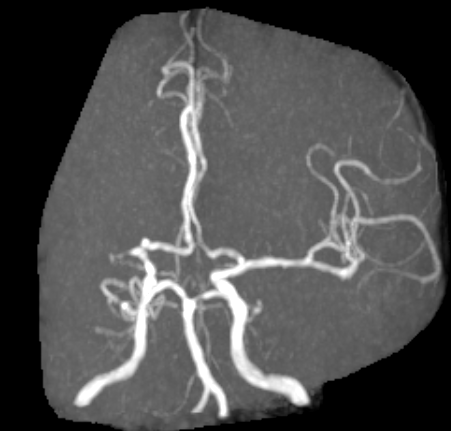

术前MR见右侧大脑中动脉M1段近端闭塞